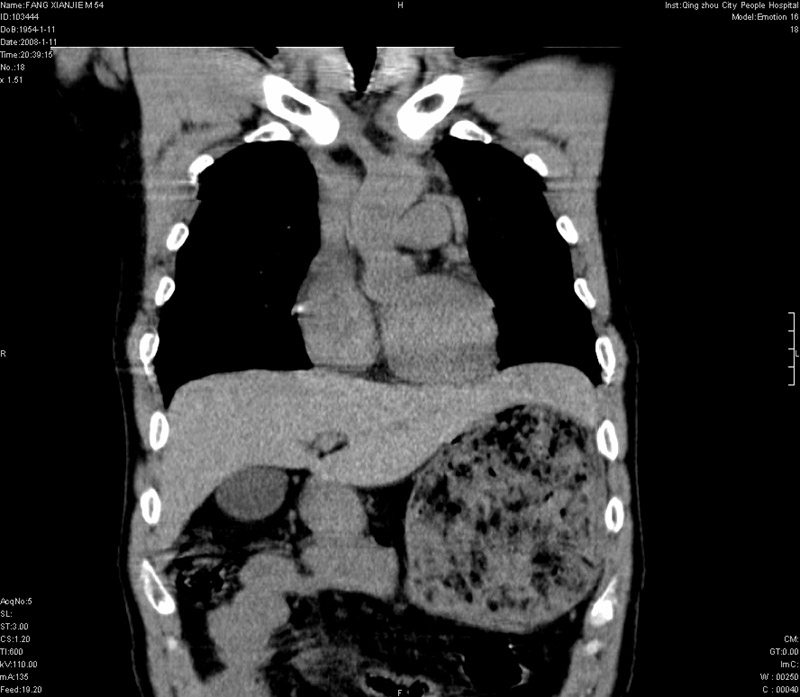

纵隔血肿,大血管破裂?左侧胸腔积血,胸骨柄骨折,冠状位示双侧第三肋骨折.

2、胸骨柄骨折,冠状位示双侧第三肋骨折.

ct11308:胸部外伤1小时(证实病例) (2008-1-13 16:2)结果如下:病人入院后两小时后症状加重,8小时后在征得病人家属同意做了ct增强扫描。如下图。最终临床诊断:外伤性胸主动脉破裂并纵隔内血肿。由于有运动性伪影,胸骨在矢状面重建的图像似有骨折征,这是一种假象,我们称之为“假骨折”,这在多层ct重建中经常性遇到,必要时要结合横断图像鉴别之。现在,病人的一般情况较差,是否要手术家属尚有争议,如果手术修补,难度较大,需要专门预定制作固定支架。

当然,对于该病例,其它非重要的诊断还有:右侧少量气胸;左侧胸腔积液;左侧轻度肺挫裂伤。对于纵隔内血肿,我们曾经遇到过多例,也有怀疑主动脉的破裂,但是,均未得到具体出血部位的明确诊断。